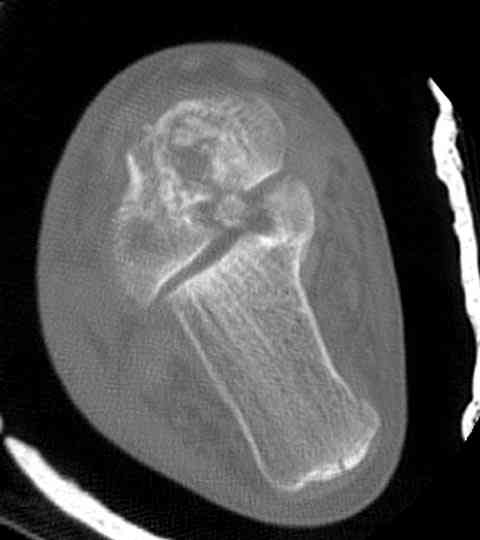

Случай с множественным оскольчатым переломом тарана оперированный из двойного доступа.

Через 14 мес.: